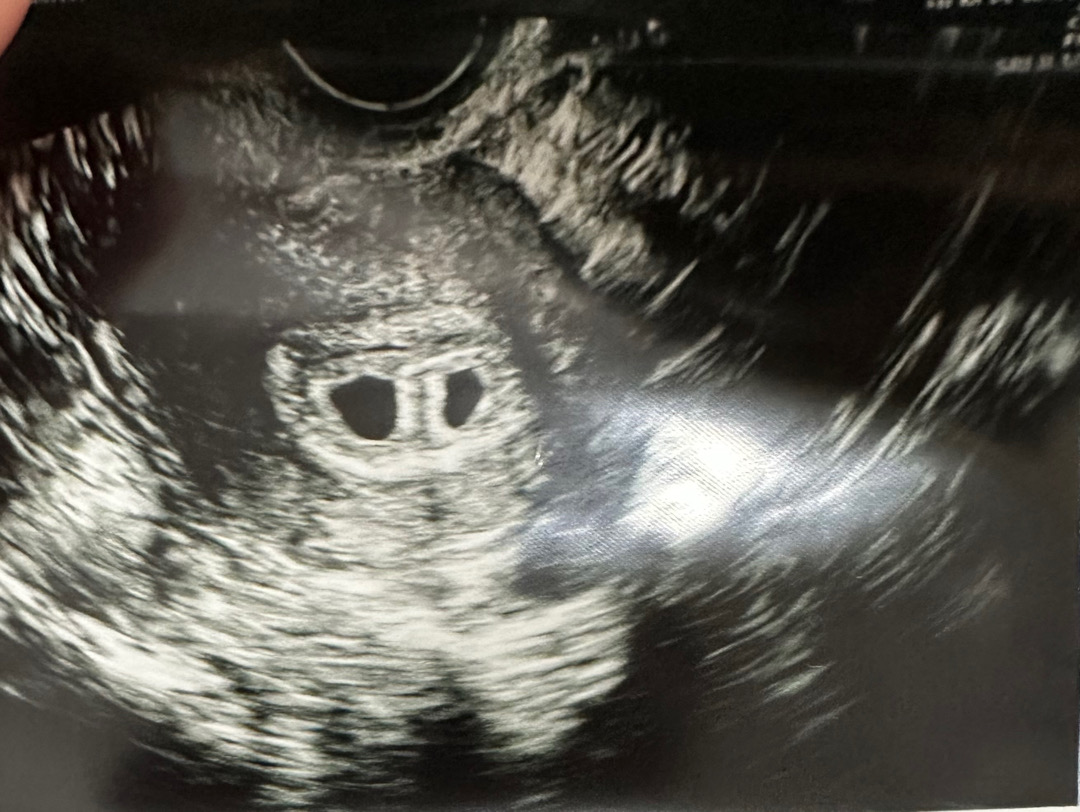

축하드려요!!!!쌍둥이!!!

5주차 쌍둥이에요!

시험관 시작하고 교수님 권유로 5배 2개 이식했어요, 배아 상태가 썩 좋지 않았던 게 이유였어요. 동결도 딱 2개 있었고.. 나이도 물론 있고요! 첫 시도였는데 이식날부터 느낌이 묘하더니 첫 피검(11일) 1169, 2차 피검 (13일) 3116으로 심상치 않은 수치를 보여줬는데, 결국 쌍둥이 판정 받고 난황까지 보고 왔어요! 15일에 심소 들으러 오라네요.. 😮 초음파실에서 너모 당황해서 한동안 멍했지만 그래도 기쁘게 받아들였습니다! 둥이 모두 잘 지켜내는 게 제 몫이라 열심히 눕눕 중이에요. 문제는 이제 5주밖에 안되었는데도 벌써부터 배멀미가 엄청나게 시작된 점.. 입덧캔디도 효과가 없고 매일 냉면만 먹고 있어요 ㅠ 입덧에 좋은 게 더 뭐 있을까요? 또 쌍둥이 부모님 계시면 반가울 것 같아요 🩵